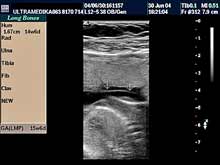

C) III trimestar trudnoće

od 24. do 40. nedelje trudnoće

Indikacija za ultrazvučni pregled:

- Procena funkcije bubrega, organa abdomena, srca i cirkulacije likvora

u mozgu.

Napomena: Na svakom pregledu do kraja trudnoće.

- Procena relativnih i organskih suženja sabirnog sistema bubrega i

izvodnih kanala bubrega i mokraćne bešike.

Napomena: Obavezna primena

3D Sono CT i XRes.

- Od 28. nedelje procena spuštenosti testisa.

Napomena: Ova informacija

je ključna za lečenje u slučaju izostanka dospevanja testisa u skrotume u toku trudnoće.

- Od 34. nedelje gestacije procena epifiza kolenih zglobova. Napomena:

Ključna informacija u slučaju postojanja bolesti štitne žlezde ploda

koja je praćena zastojem razvoja inteligencije nakon rađanja bebe.

- U slučaju zastoja porasta ploda procena redistribucije krvotoka i

određivanja termina porođaja.

Napomena: Tačnost je zasnovana na

primeni Broadband Color Dopplera i Color Power Dopplera.